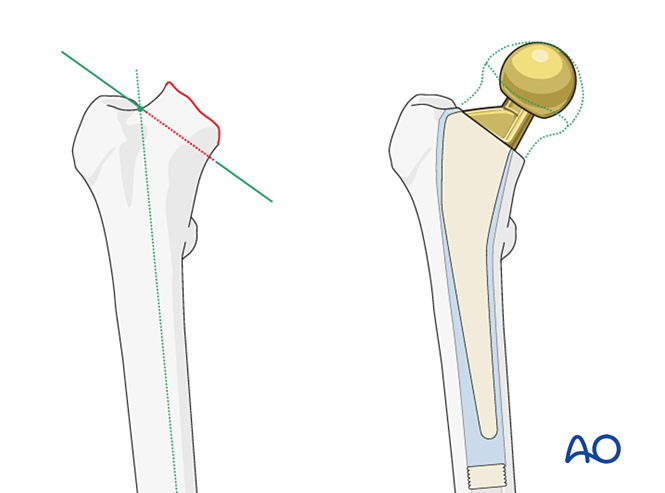

股骨颈截骨截骨平面影响假体高度,需确保下肢等长及软组织张力。

截骨方向依假体设计:始于大转子下窝,止于股骨距区。若假体带内侧翼,截骨需匹配翼部位置。

陷阱:股骨颈过短股骨偏距不足将导致肌张力不足,增加术后脱位或外展肌无力风险。需术前精细规划。假体旋转对位假体需与股骨颈轴线一致(图示“β”角为前倾角)。避免过度前倾(前脱位风险)或后倾(后脱位风险)。髓腔锉磨时保持目标前倾角以实现旋转对位。